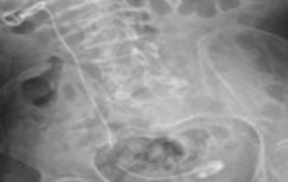

Ender Cem Bulut, Mahmut Uğurlu, Mustafa Kaba

Double-J (DJ) stents are essential tools in various urological

procedures []. With the increasing frequency of DJ stent use,

stent-related morbidities have become more prevalent. In the

short term, complications such as pain, irritation, infection, and

hematuria may occur. In the long term, serious complications

including encrustation, urolithiasis, stent migration, fracture,

renal damage, and even death have been reported []. DJ

stents may require removal through extracorporeal shock

wave lithotripsy (ESWL), cystolithotripsy, laser lithotripsy,

percutaneous nephrolithotomy (PNL), open surgery, or

combinations of these approaches [].

Cerebral palsy (CP) is a neurological disorder affecting

motor function and is frequently associated with urological

complications, particularly lower urinary tract dysfunction [].

The management of urolithiasis in patients with CP is often

challenging due to physical disabilities, anatomical variations,

and accompanying comorbidities [].

Fractured DJ stents are rare clinical occurrences. In this case

report, we present the endourological management and singlesession

removal of a severely encrusted DJ stent that remained

in situ for approximately 2.5 years.